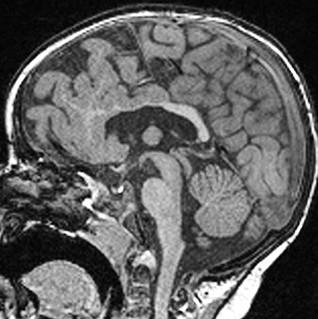

Sag T2 Cube nongated Normal

Normal

Sag T2 Cube

Nongated: CSF dephasing in the aqueduct on this sequence

Primary fissure 3 lobes Closed fastigial point

Sag T2 Cube Normal

Anterior commissure

Corpus Callosum

Rostrum, genu, body, splenium

Sella/Suprasella

ON, post pit bright spot, stalk

Midbrain

Patent aqueduct

Pons

“just right…”

Vermis

3 lobes

Cerebellar Tonsils